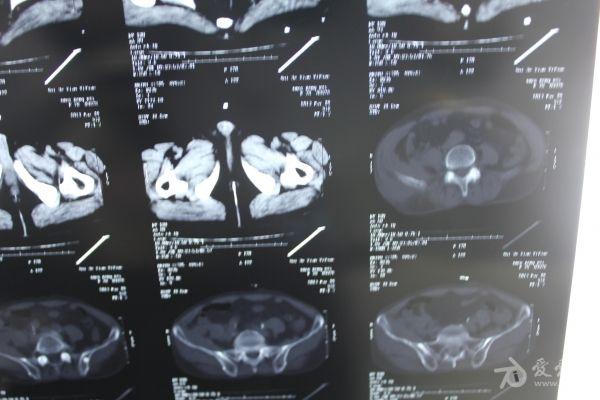

老年患者78岁,反复腰背部溃烂流脓4年,既往30年前曾在包块处排出蛔虫一条。CT: